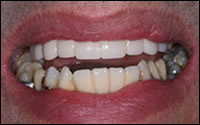

Fig 5: Before and After.